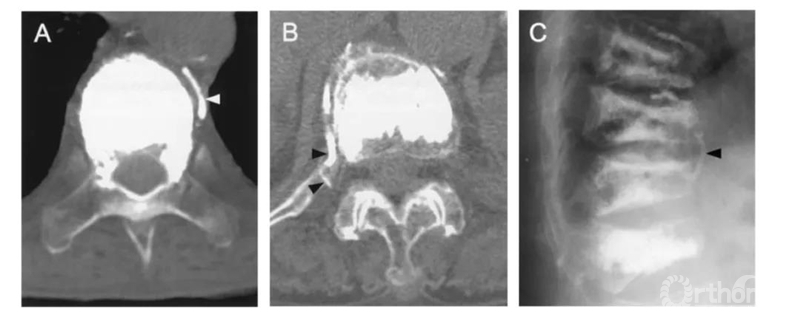

该患者做完PVP术后失血性休克症状。复查CT发现巨大的腹膜后血肿。血管造影发现L2左侧节段动脉远端破裂,行栓塞修复。

三维CT显示椎旁节段动脉就在椎体旁正中走行,所以椎弓根外侧穿刺安全边界在椎弓根中线以上。